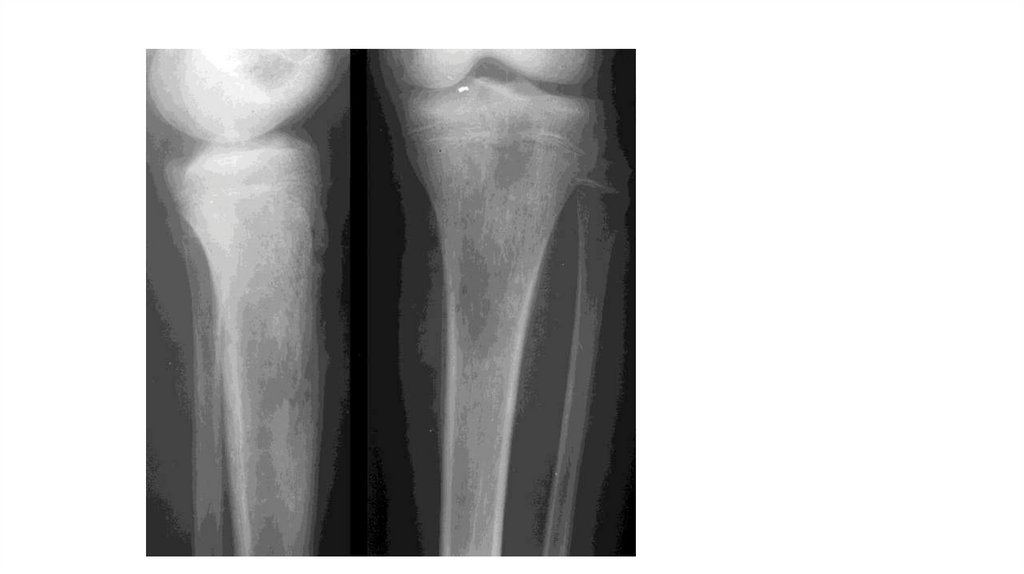

Воспалительные заболевания опорнодвигательного аппарата

«Воспалительные

заболевания опорнодвигательного аппарата»